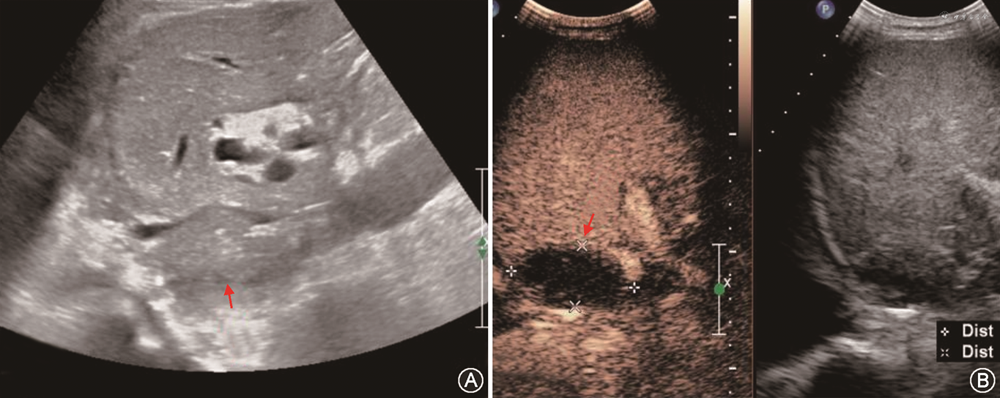

1. 肝移植术后胸腔、腹腔及肝周积液:移植后早期在双侧胸腔肋膈角、下腹部、肝裸区或肝包膜下常可探及少量透声良好无回声区,一般短期内可逐渐吸收。陈旧性或感染性积液多透声差且流动性弱,其内可见密集点状回声及粗细不等分隔,部分可呈蜂窝状或高回声的实性团块。CDFI检查内部无血流信号,超声造影检查内部始终无造影剂填充[47](图10)。超声造影检查如观察到造影剂自血管溢出,可帮助发现活动性出血[33]。当积液量较大患者症状明显或影响器官功能时,可行超声引导下置管引流术,在改善患者症状的同时有助于明确积液性质[48]。

(1)PVT:PVT多发生于肝外门静脉段或门静脉吻合口。肝移植前受体有PVT病史、门静脉内径较细(<5 mm)、患者处于高凝状态及有脾切除手术病史等是好发因素[47,51,71]。移植肝PVT声像图表现为门静脉管腔内见实质回声,CDFI显示血流充盈缺损或不能测及彩色血流。急性PVT灰阶超声上有时可呈无回声表现,需结合CDFI检查进行鉴别。当CDFI检查门静脉血流显示不清时,应用超声造影可以改善门静脉的显示,明确门静脉是否闭塞(图17)[33,72]。